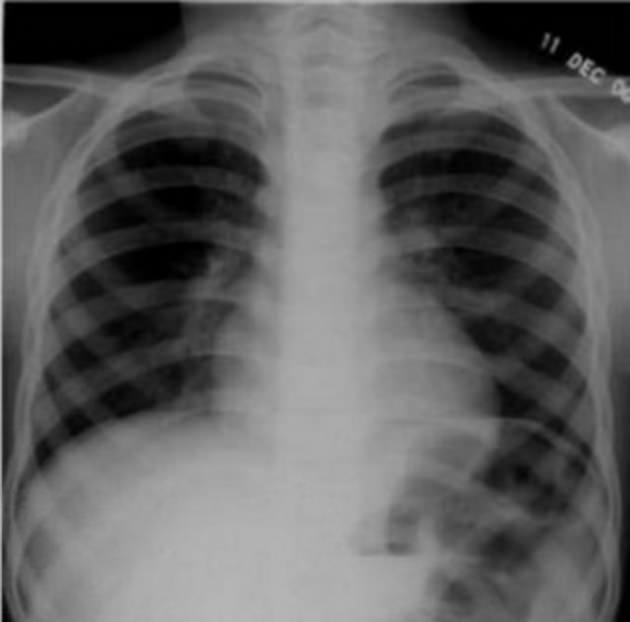

17 yaşındaki genç kızın karnından çıkarılan madeni nesnelerin arasında jilet ve çiviler de bulundu.